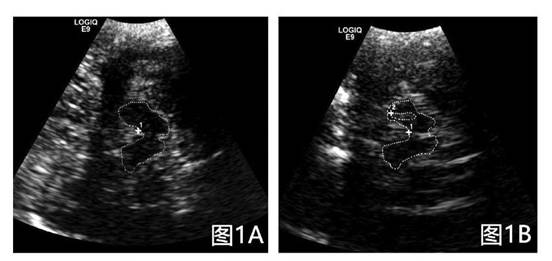

黑质超声图像清晰直观,左图为正常人群黑质体,右图为帕金森患者黑质体